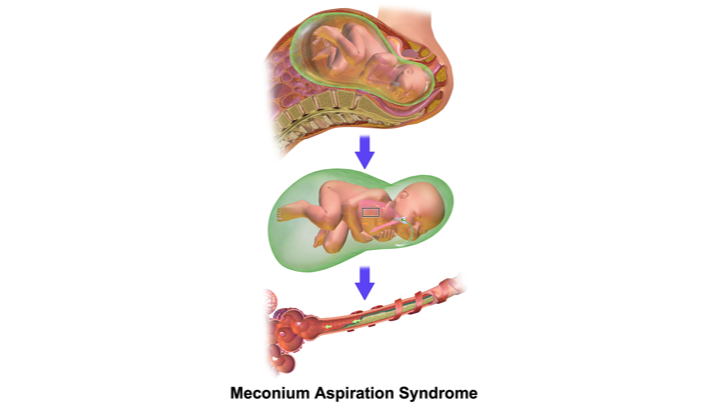

Медицинские аспекты мекония в околоплодных водах